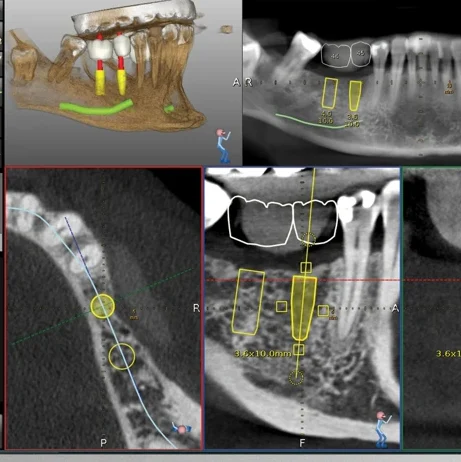

| 1. 初診諮詢 | 評估口腔狀況、全口X光、3D電腦斷層掃描 |

| 2. 數位規劃 | 模擬植體位置、分析骨量、製作導引模板 |

- 是否使用3D電腦斷層與導引模板?

我們會透過3D電腦斷層,精準了解骨頭狀況,並客製你的治療計畫。 - 植牙手術(1次門診)